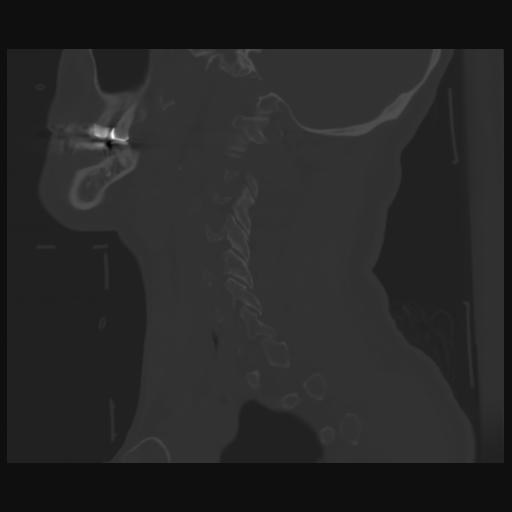

14 P.BLANDAS,,Sagittal,2.000,P.BLANDAS,Sagittal,